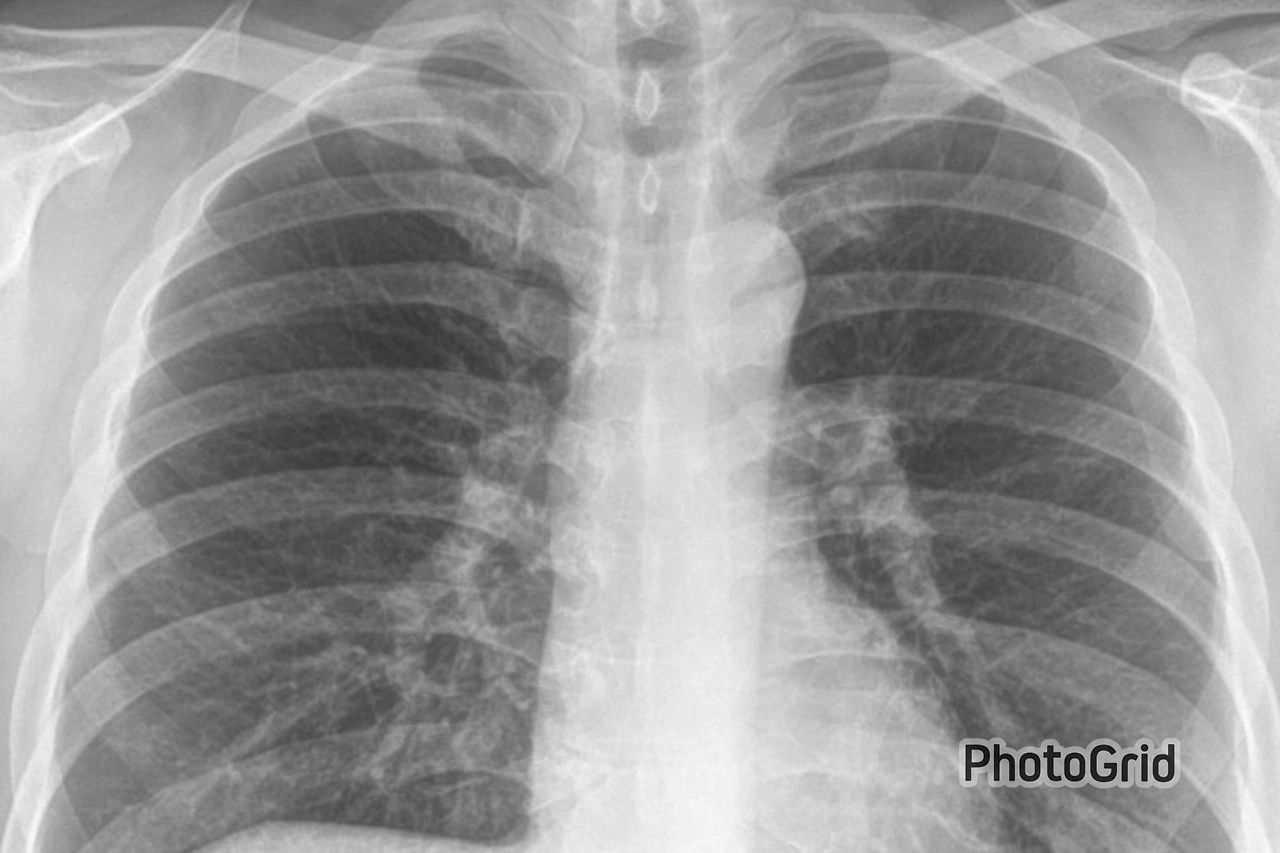

며칠 후, 학교 내 보건진료소에서 합격자 신체검사가 시작되었다. 신체검사 항목 중 다른 것은 문제가 될 게 없었다. 나는 초조한 마음으로 X-ray 촬영대에 올라섰다. 그 시절의 흉부 X-ray 사진은 간접촬영방법을 채택하고 있었는데, 조그맣게 찍은 필름을 확대하여 판독하는 방법이었다. 이 방식에 의해 결핵이 의심되면 직접촬영대상자로 분류되는 것이다. 당연히 나는 직접촬영대상자로 호출되어 또다시 가슴사진을 찍어야 했다.

다음 날, 두근거리는 가슴으로 보건진료소 문을 밀고 들어갔다. 좁은 진료실에서는 머리가 하얗게 센 의사가 왼손으로 안경을 약간 들어 올린 채 X-ray 사진을 열심히 관찰하고 있었다. 하얀 형광등 불빛의 판독대에 시커멓게 붙어 있는 X-ray 필름에는 붉은 색연필로 다음과 같이 쓰여 있었다.

‘활동성 공동성 중등증'

당시 활동성 폐결핵환자는 전염 가능성 때문에 학교든 군대든 갈 수가 없었다. 나는 사회로부터 격리되어야 할 대상이었던 것이다. 더구나 결핵균이 폐 조직을 파먹어 허파에 구멍이 생겼다는 공동성(空洞性)이라는 단어는 나를 더 낙담하게 만들었다. 더 이상 할 말을 잃은 나는 고개를 푹 숙인 채 보건진료소 문을 밀고 나섰다. 젊음으로 가득 찬 캠퍼스에는 늦겨울의 한기가 마지막 기세를 떨치고 있었다.